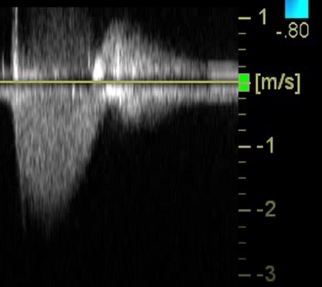

Was attempting to align the image for Aortic PWD Trace to calculate CO. Marked turbulence seen. Further look on PSAX showed this:

You could see the turbulent flow originating from the edges of the posterior leaflet.